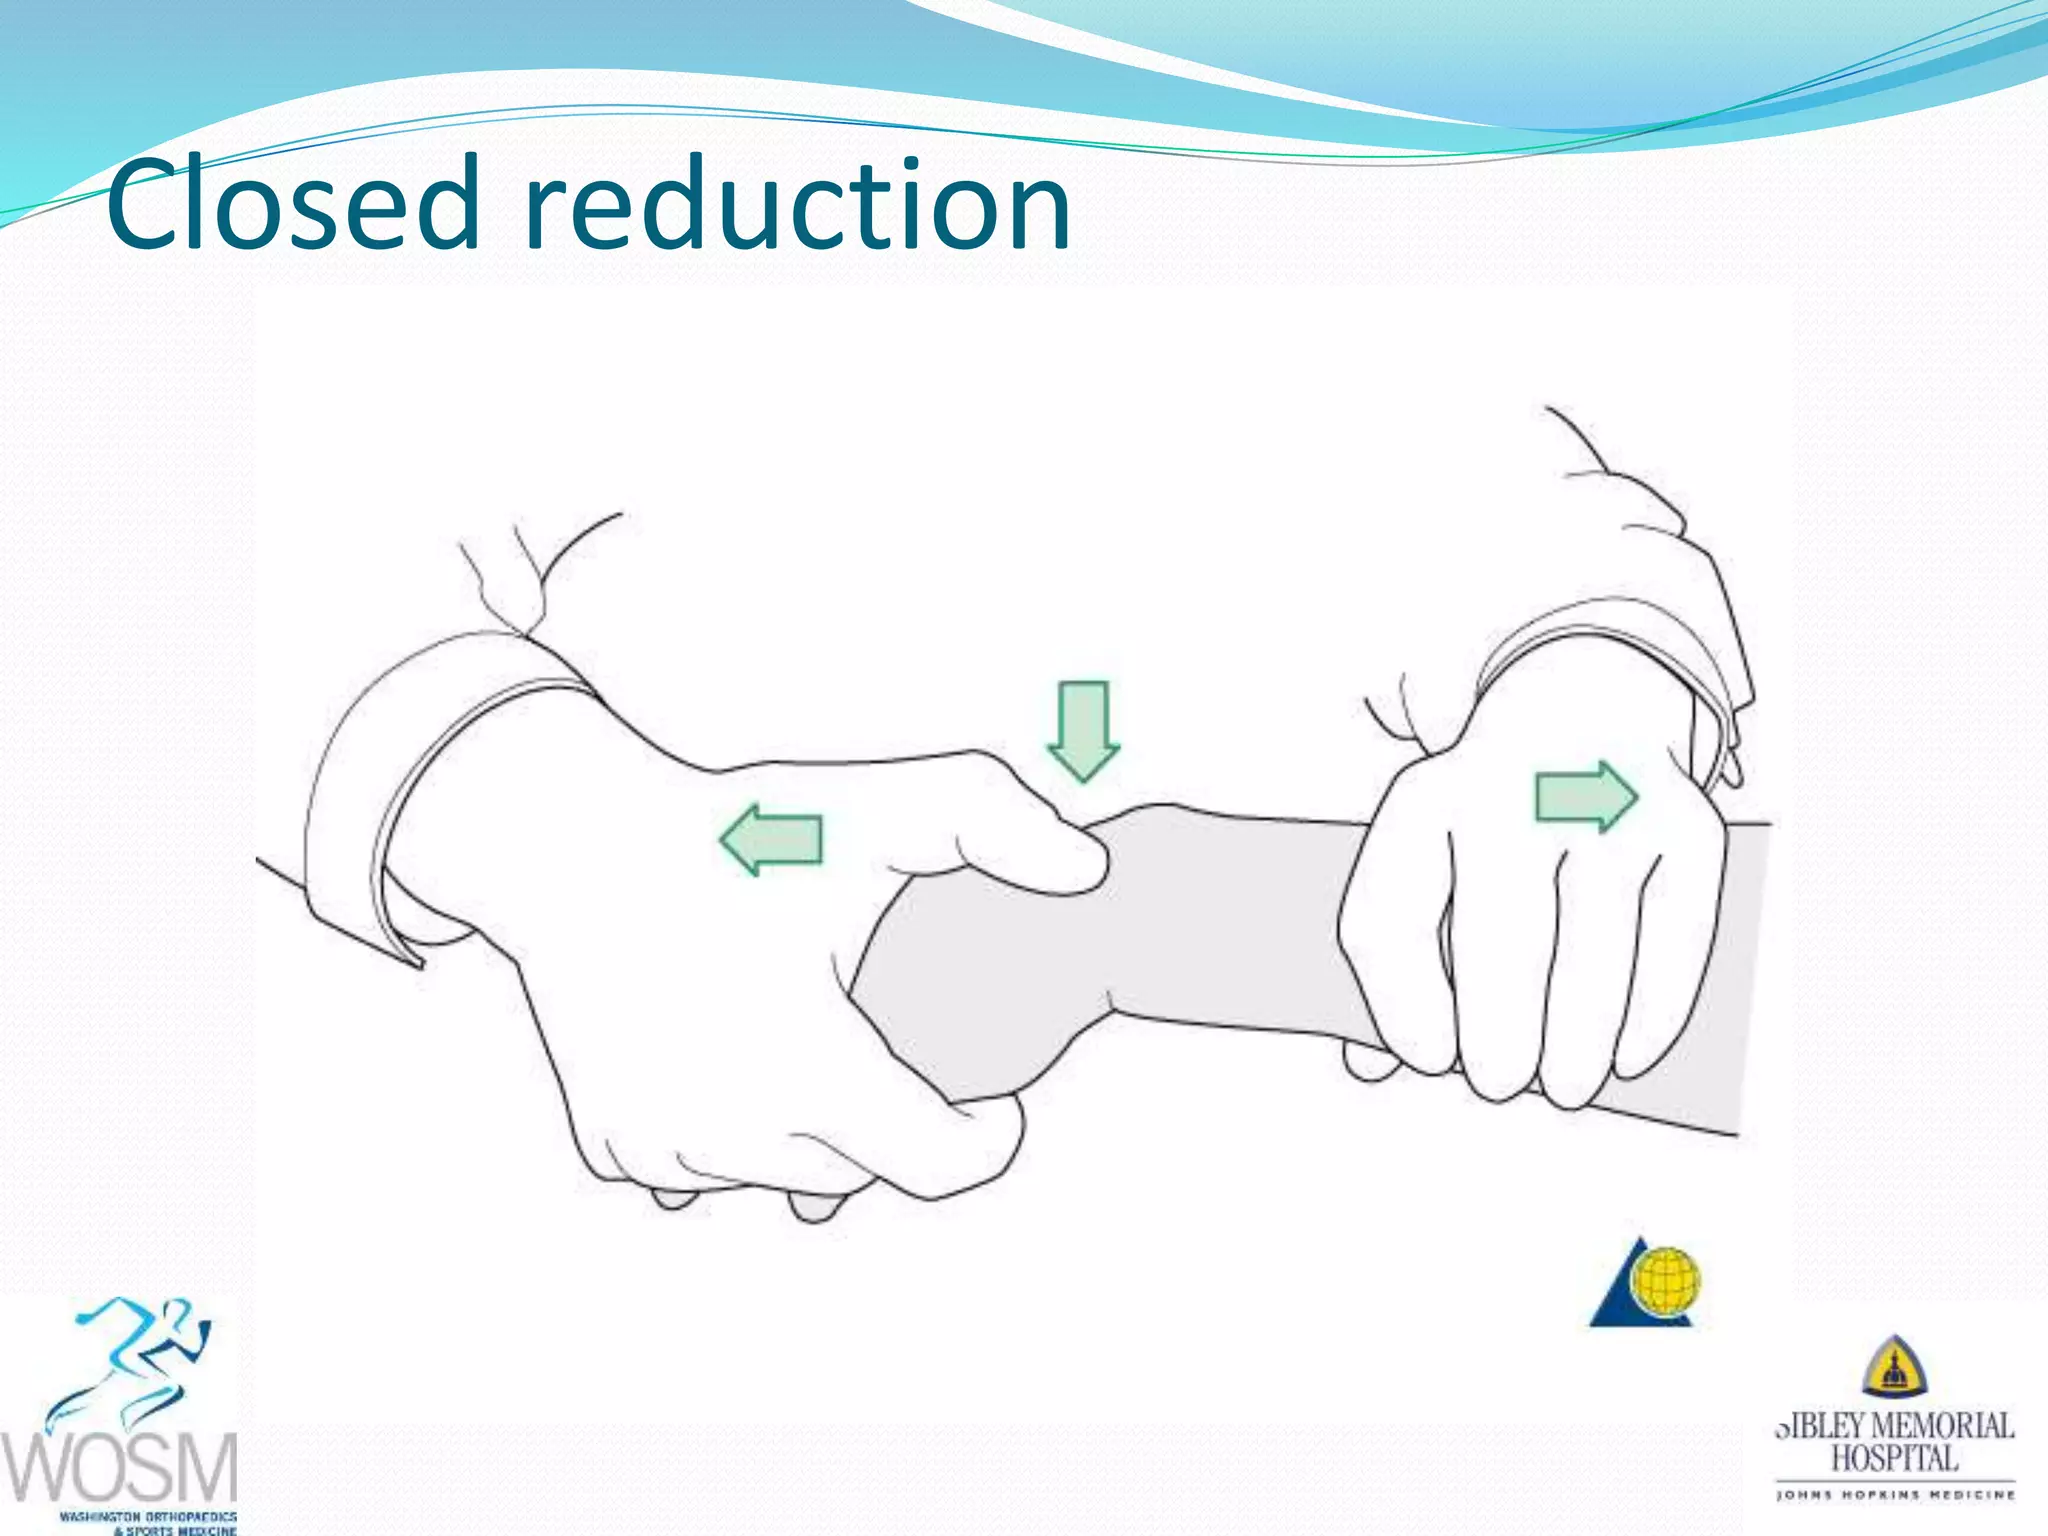

This document discusses wrist fractures, including who is most at risk, common causes, signs and symptoms, treatment options, and prevention. The elderly and those with osteoporosis are most prone to wrist fractures due to falls. Treatment may involve splinting, casting, closed reduction, or surgery depending on the fracture. Maintaining bone health through medication, vitamins, exercise, and diet can help prevent wrist fractures.